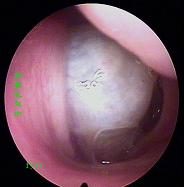

鼻炎长期得不到有效治疗导致鼻息肉以及鼻腔囊肿

一、基本检查:1.前鼻镜检查。2.X线鼻泪管造影,明确有无并发鼻窦感染。